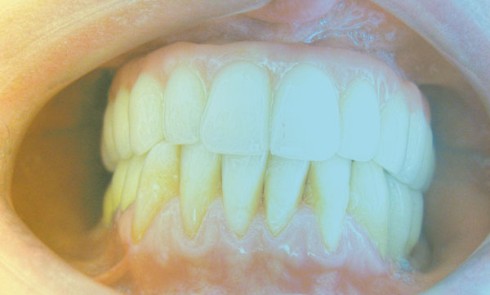

Article réservé à nos abonnés Parodontie et prothèse

Les relations qui unissent prothèse et parodonte sont souvent conflictuelles et complexes. Afin d’éviter ces conflits entre impératifs prothétiques et...